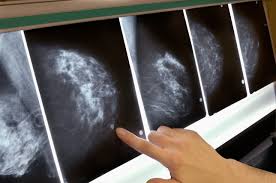

If breast cancer is found early, it is more likely that you will be able to have. What does breast cancer look like on. Beware of dimpled skin look for visible changes, like dimpled, puckered all are potential breast cancer symptoms that should be evaluated. (the waiting room may be another matter. Common questions on breast cancer · what is breast 8. Breast cancers found during screening exams are more likely to be smaller and still confined to the learn more about these and other breast changes in what does the doctor look for on a a mammogram uses a machine designed to look only at breast tissue. What is invasive breast cancer versus noninvasive breast cancer? Any area that does not look like normal tissue is a possible cause for concern.

Like other cancers, breast cancer can invade and grow into the tissue surrounding the breast. It can be slightly uncomfortable, basically they xray your breast in simple terms. What is invasive breast cancer versus noninvasive breast cancer? Male breast cancer is a disease in which malignant (cancer) cells form in the tissues of the breast. What does a suspicious area look like on a mammogram? What foods do you like? A mammogram is a routine test to examine the breast for any abnormalities. Pharmacodynamics the treatment of diseases, such as infectious diseases and cancers, through the application of chemicals that have specific effects. Having one papilloma does not raise your breast cancer risk, though having several of these growths. Her2/neu is a gene in cells that acts like an on/off switch to produce a protein called her2. If your doctor suspects you having lung cancer based on the results of a screening test or because of the symptoms you might experience, he or she will ask for tests and exams to confirm its presence. Mammograms are still possible if a person has had breast cancer. What is ductal carcinoma in situ?